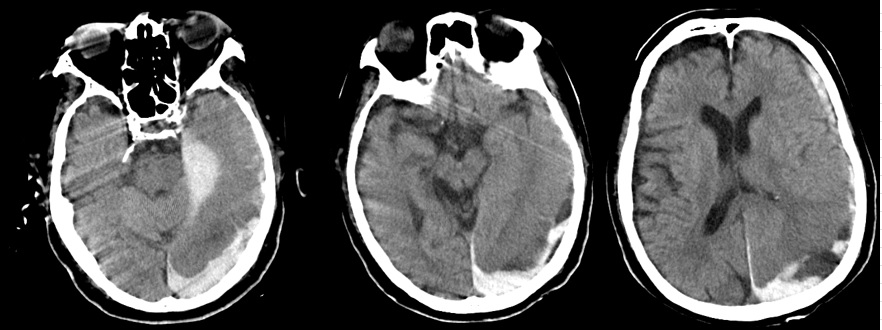

- 9月12日:急性硬膜下血腫

死亡した日の頭部CTで重度の急性硬膜下血腫が認められる。「その原因はDICによる出血傾向」と岩井医師は説明したが、 下記に示すように、この日の血液検査では出血傾向は軽度であり、頭蓋内への自然出血は否定される。

証拠:頭部CT・急性硬膜下血腫

- 9月12日:出血傾向はごく軽度

PT-INR 1.3, APTT 35 sec, 血小板3.6万/μl, Hb 8.2 g/dl:出血傾向はごく軽度で硬膜下血腫の自然発生は否定的。この時、父は意識がなく自ら動くことはできない状態であったため、残る可能性は頭部外傷のみ。

この時、撮影された頭部CTで急性硬膜下血腫が認められた。これが父の直接の死因となった。 岩井医師からもその説明があったが、 直接の原因と推定される「頭部打撲」には一切言及がなく(録音記録あり)、 DIC(播種性血管内凝固)に伴う出血傾向による自然出血とのことだった。 しかしこの日、数時間以内に行われた血液検査では、「PT-INR 1.3, APTT 35 sec, 血小板3.6万/μl」と 出血傾向はごく軽度であり、自然発生的に頭蓋内に出血を起こす可能性は皆無と言ってよい。

このことから、直接の死因である急性硬膜下血腫の原因は頭部打撲と確定できる。 この時点で父の意識はなく、自ら動くことは全くできない状態であることから、 頭部打撲は外力によって起こったという結論に達する。つまり変死である。

この時、同時に撮影された胸腹部CTでは、大動脈周囲に三日月状の血種様の病変が認められ、両胸腔にはフィブリン化したと思われる血餅の残存病変が多数認められた。血管損傷に伴い胸腔に出血していた証拠であり、当初のPCI(カテーテル治療)での大事故の痕跡がこのCT画像に残っている。